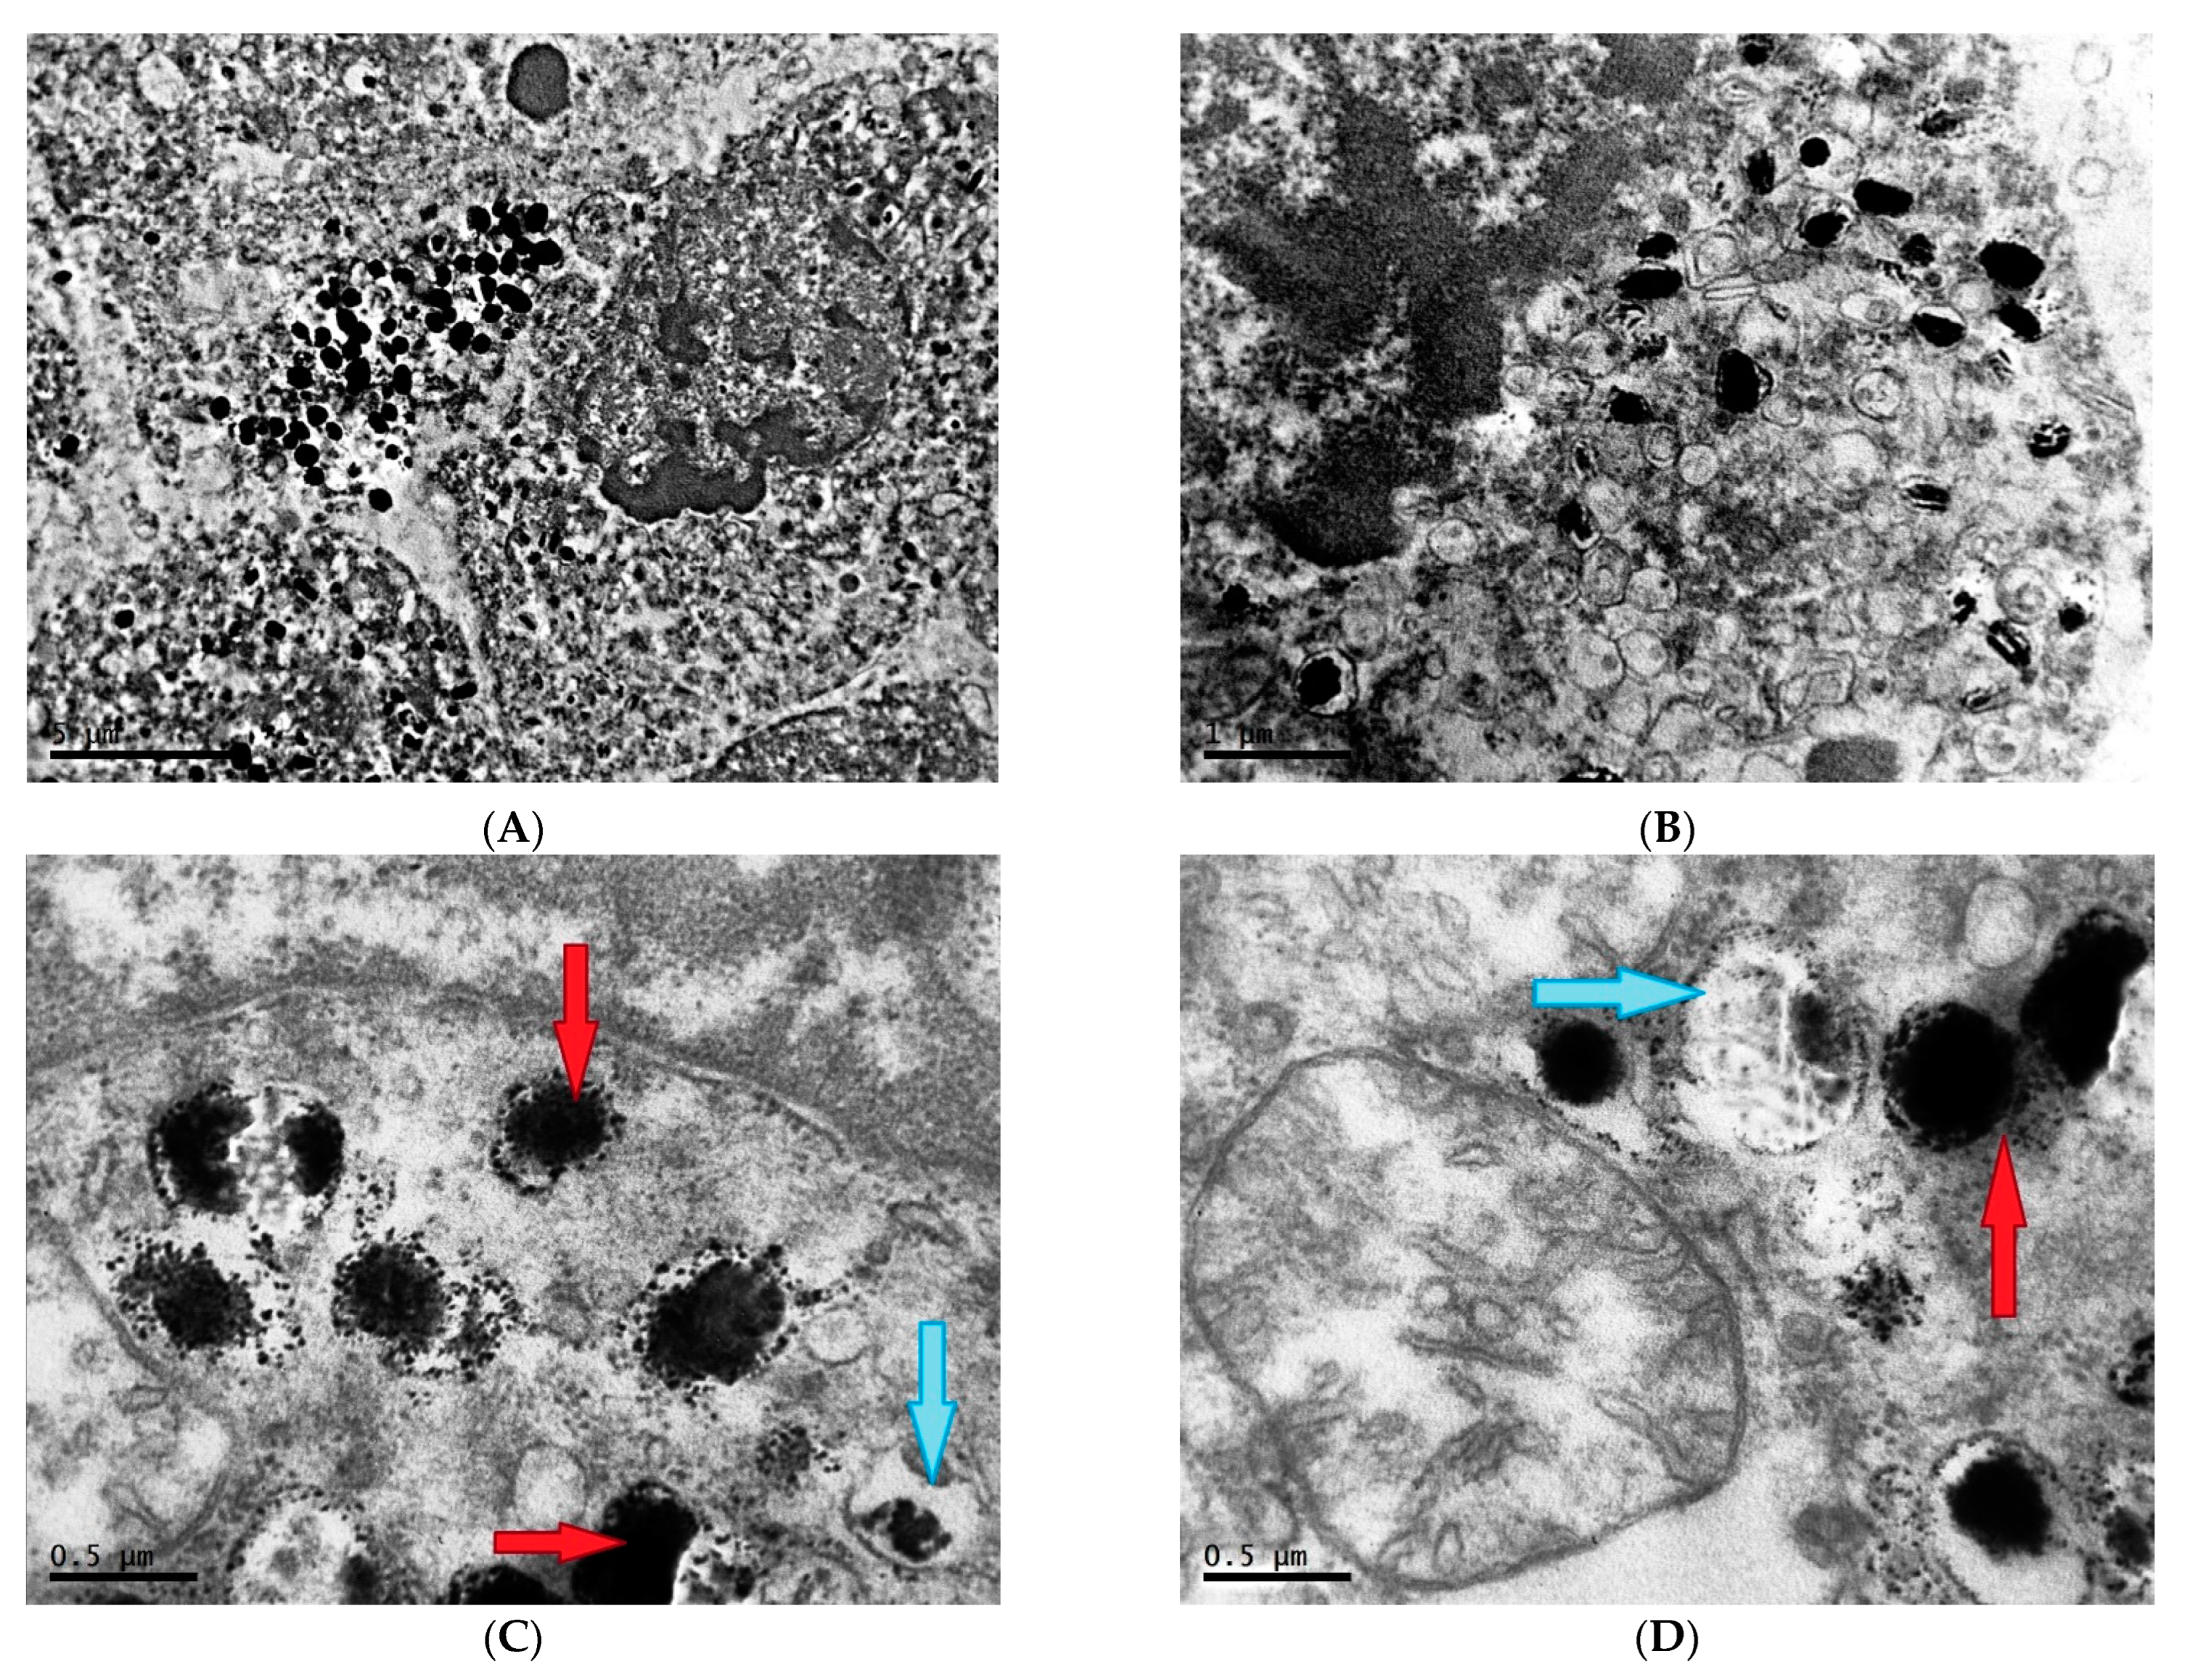

2.2. Ultrastructure of Transplantable Malignant Melanoma B16 in Conditions of Constant Lighting Regime